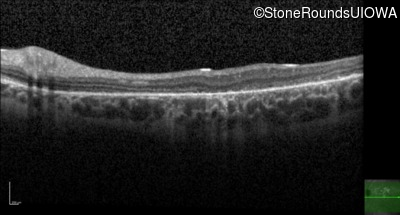

Age at visit: 26 years

Age at visit: 27 years

Age at visit: 31 years